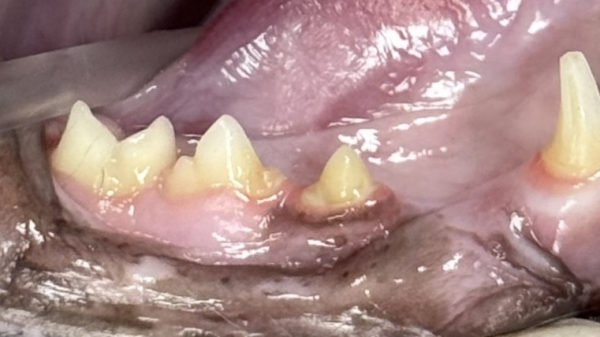

진료 중 확인해보니 고양이는 치석과 치은염이 있었고,

육안상으로도 307번 치아에

치아흡수병변이 의심되어,

→ 문제가 있었던 307번과 407번 치아는

surgical bur를 이용해 절삭 후

발치를 진행했습니다.